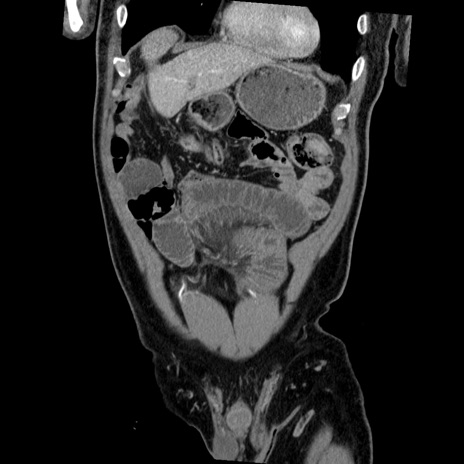

症例

横断像